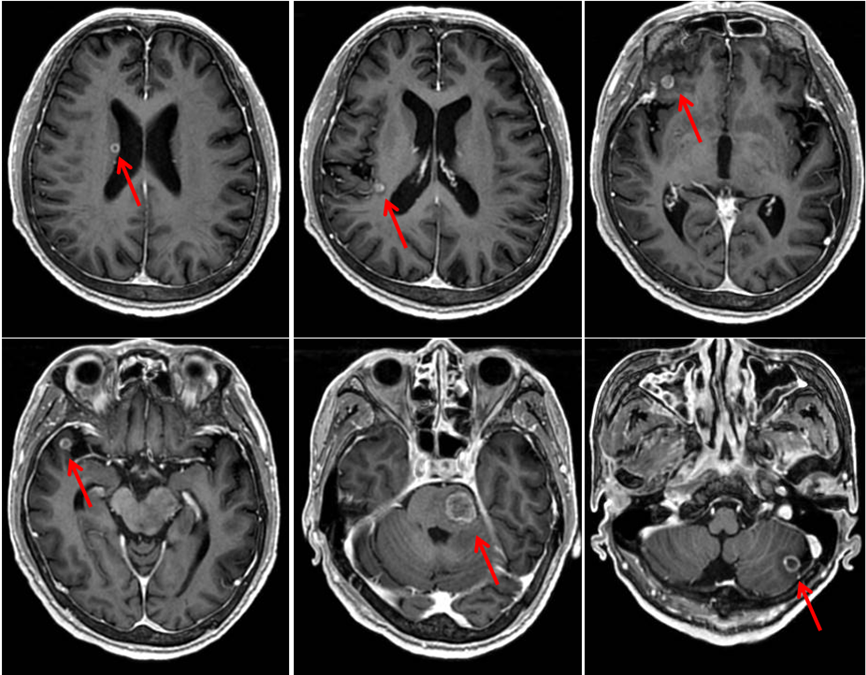

完善顱腦強(qiáng)化MRI檢查示:腦干、左側(cè)小腦半球、右側(cè)額顳葉、右側(cè)基底節(jié)放射冠區(qū)多發(fā)占位性病變,符合轉(zhuǎn)移瘤表現(xiàn)(圖2)。

圖2.腦干、左側(cè)小腦半球、右側(cè)額顳葉、右側(cè)基底節(jié)放射冠區(qū)多發(fā)占位性病變。